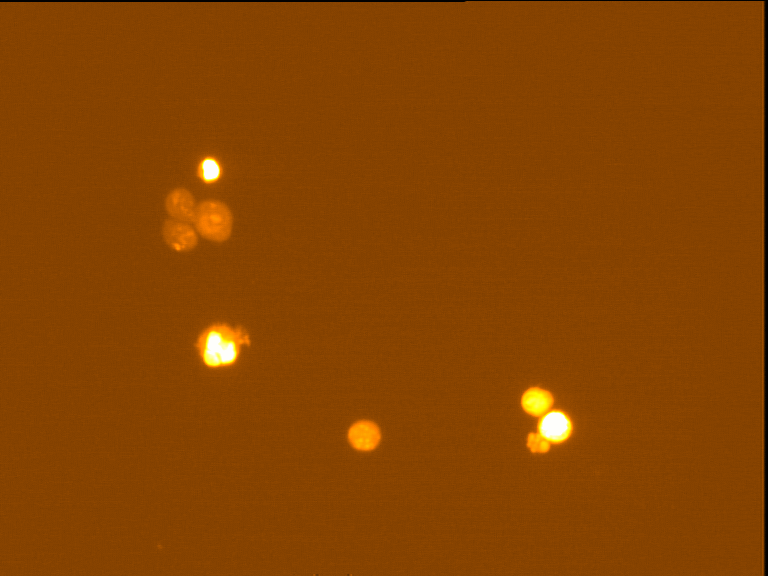

Fig. 4 through 6 show the morphological features of Raji cell sub-lines exposed to DOX, indomethacin, or verapamil. Some of the reversal agents significantly increased the frequency of apoptotic cells compared with control cells. Thus, the P-gp reversal agents were able to overcome apoptotic resistance in the NHL cell-line model. Apoptotic cells in the controls contributed approximately 10% of the whole population (i. e., 61/600 x 100 = 10.16% for TK+ and 69/600 x 100 = 11.5% for TK-). After exposure to the P-gp reversal agents, apoptic cells increased to 22.3% with indomethacin and to 43% with doxorubicin in TK+ cells. In TK- cells, apoptic cells increased from 11.5% to 26.8% and 75.7% with indomethacin and doxorubicin, respectively.

Fig. 4: Comet images of the Raji cell sub-lines after treatment with 25 nM DOX for 48 hours in 37°C and 5% CO2. TK+ treated cells (left). And TK- treated cells (right), as photographed with the Leica microscope below X 200

Fig. 5: Morphological features of Raji TK+ cells after treatment with indomethacin (1), verapamil (2) and DOX (3). In each row, left images show intact cells, middle images show apoptotic cells, and right images show necrotic cells as they appeared under the microscope X 200